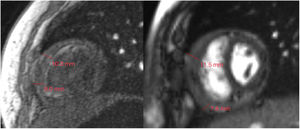

Abordaje diagnóstico y terapéuticoSe inició manejo para la insuficiencia cardiaca derecha con oxígeno, diuréticos y restricción de líquidos. El ecocardiograma demostró pericarditis constrictiva con disfunción diastólica del ventrículo derecho y patrón restrictivo en el ventrículo izquierdo. Se realizó resonancia magnética cardiaca donde se corrobora diagnóstico y se demostró un pericardio de un grosor de 12mm con compromiso hemodinámico importante (fig. 1).